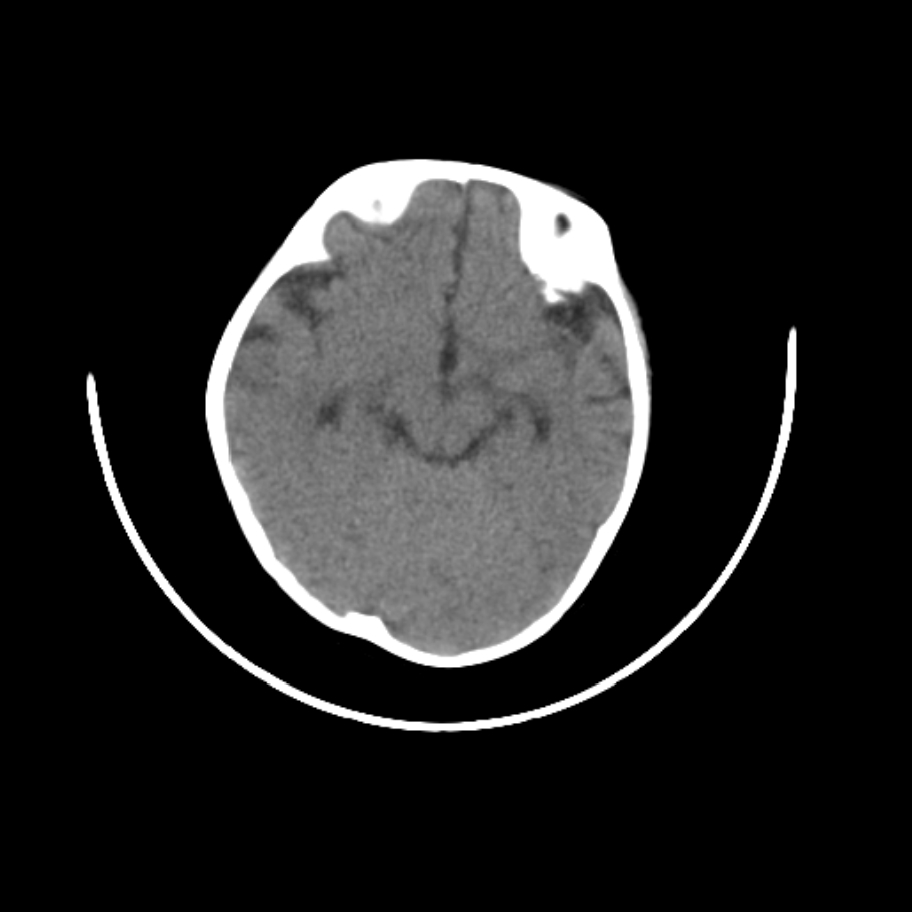

以下是引用随光逐影在2009-4-8 7:51:00的发言:[br]1)透明隔缺如(视-隔发育不良?)。2)右侧脑裂畸形。3)右侧幕上半球脑萎缩。